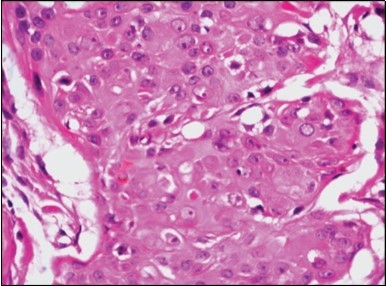

Figure 4.Cellular atypia, mitosis and focal necrosis in eccrine porocarcinoma(16).

Cellular atypia, mitosis and focal necrosis in eccrine porocarcinoma(16).